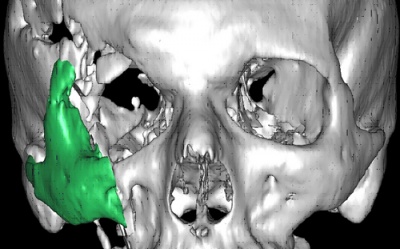

Per radiografia si intende lo studio, il più dettagliato possibile, di un segmento scheletrico o di un distretto, attraverso l'utilizzo di radiazioni elettromagnetiche di tipo x, dette anche ionizzanti, per la loro proprietà di emettere ioni. E' questo un antico, ma pur sempre valido esame di primaria importanza, quando viene utilizzato in circostanze particolari, come in un incidente, per valutare gli eventuali danni articolari o in caso di trauma cranici; in casi di emergenza rappresenta la principale fonte d' informazioni, in quanto la consultazione risulta estremamente dettagliata e chiara.

Si riprodurrà quindi una immagine del tutto simile al corpo, ma in negativo, come una vera e propria fotografia, in quanto i fotoni che non vengono assorbiti, restano impressi sulla pellicola. L'esame a raggi x, in grado di fornire immagini di strutture anatomiche, per scopi diagnostici, consiste in effetti nell'imprimere su una pellicola radiografica le diverse densità dell'organismo, la pellicola risulterà più o meno scura a seconda della struttura rilevata. Tutto ciò avviene perché, quando i raggi x attraversano la materia, producono ioni, la nitidezza dei particolari degli organi interni che appaiono diversamente opachi, è dovuta alla loro composizione ed alle proprietà più o meno di assorbimento.

Nell'apparato osteo articolare è possibile rilevare:

- Fratture,

- Tumori,

- Fare delle valutazioni di osteo artrosi,